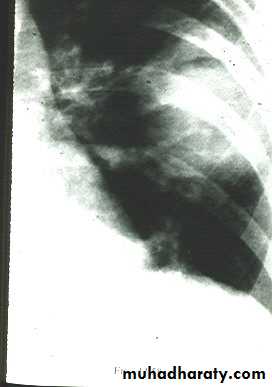

rt.upper lobe pn. Left lower lobe pn.